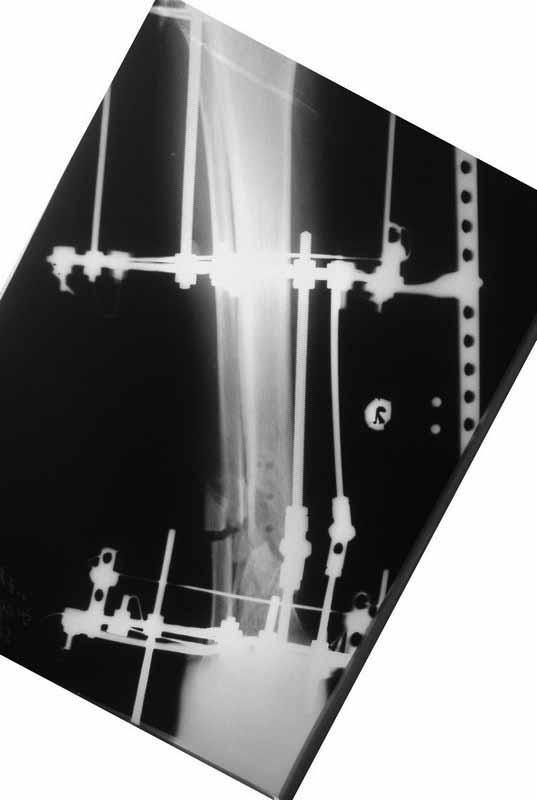

Боюсь, кусок гвоздя в канале будет сильно мешать, так что мы бы открыли бы над ним передне-медиальную кожно-надкостнично-костную "крышку", и убрали. То есть не скелетировать чтобы кость даже вдали от несращения.

А так - согласен с Алексеем, аппаратная репозиция (если тугоподвижность - то за несколько дней), зону несращения не открывать, рассверлить, помыть, стержень с антибактериальным цементным покрытием.

Если свищи - может, действительно спейсер на насколько недель сначала.

(АС) Если нет данных за инфекцию в зоне перелома мы бы аппараптом дозированно устранили деформацию и, не удаляя дистальный фрагмент сломанного гвоздя,

(АЧ) Боюсь, кусок гвоздя в канале будет сильно мешать, так что мы бы открыли бы над ним передне-медиальную кожно-надкостнично-костную "крышку", и убрали. То есть не скелетировать чтобы кость даже вдали от несращения.

Подвинуть новый гвоздь обломок сможет, а вот блокировать может не дать. Мы и отломок гвоздя попробовали бы удалить закрыто.